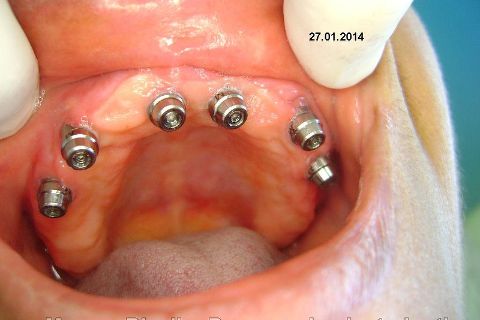

Atualização do caso clínico que já postei, "REABILITAÇÃO EM MAXILA ATRÓFICA COM IMPLANTES", um caso que inclui expansão do rebordo estreito com cinzel e martelo, expansores rosqueáveis, enxerto e instalação dos implantes distais inclinados tangenciando seio maxilar. Inclui esvaziamento do forame nasopalatino e preenchimento com biomaterial para instalação de dois implantes próximos dele. Cirurgia realizada em única sessão, com instalação dos 6 implantes. Para os colegas que não conheceram e/ou esqueceram da apresentação, este é o resumo do caso na fase cirúrgica.http://www.youtube.com/watch?v=BtvexFexRPA&hd=1

FASE PROTÉTICA DA REABILITAÇÃO EM MAXILA ATRÓFICA...incluindo a reabertura, instalação dos minipilares e PTR provisória reembasada sobre os cilindros de proteção.